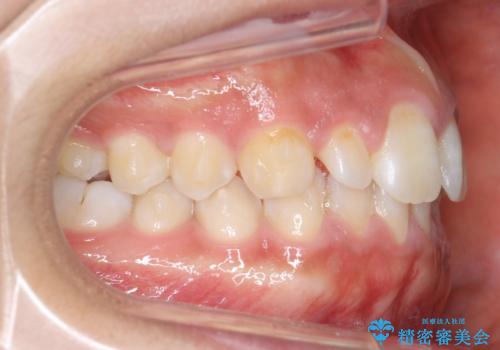

前歯のすきま 矯正治療とセラミックで小さな歯を形良く

- 前歯のすきまを気にして来院。

左上の2番が生まれつき小さく、スペースが余っていました。

右上の2番もやや小さめでしたが、相談の上、左上2番のみセラミックで形を整えることとしました。

そのほかの隙間はマウスピース矯正で閉じることにしました。